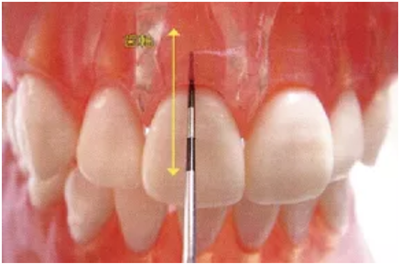

● 鄰接面正下方的探診

鄰接面的正面檢測方法。注意大約是在鄰接面部分的中央位置處,將探針略傾斜插入鄰接面的中央點。

檢測鄰接面正中點下方的牙周袋,探針是無法與牙軸平行插入的。但是緊靠著鄰接點平行于牙軸插入探針,可以檢測到難以檢測的鄰接面牙周袋深。

如果從斜側(cè)插入探針檢測沒有一定的標(biāo)準(zhǔn),那么每次測出的數(shù)值都會各不相同,得到的數(shù)據(jù)難以正確分析出問題所在。